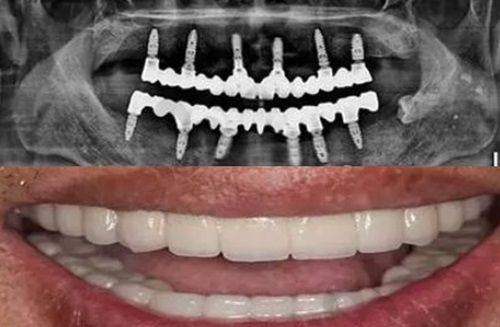

牙齿矫正适用于轻度至中度的面部歪斜。通过佩戴矫正器,对牙齿施加一定的外力,逐渐将牙齿移动到正常位置,从而改善锁颌和中线不齐的问题。矫正器的种类有特别多,如传统的金属矫正器、陶瓷矫正器以及隐形矫正器等。不同的矫正器各有优缺点,患者可以根据自己的需求和医生的建议进行选择。一般来说,牙齿矫正需要较长的时间,通常为1 - 3年,但在矫正过程中,脸部歪斜的情况会逐渐得到改善。

正颌外科手术

对于重度的面部歪斜,可能需要进行正颌外科手术。这种手术通过移动颌骨来调整牙齿的排列和咬合关系,改善面部歪斜问题。正颌外科手术是一种较为复杂的手术,需要专精的医生团队进行操作。手术前需要进行详细的检查和评估,以确定至佳的手术方案。不同情况需采取不同治疗方法,建议及时就医,在医生指导下选择合适的治疗方案。